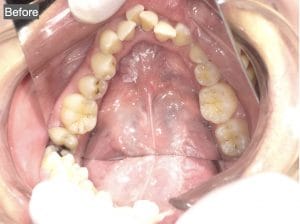

Case029

セラミック矯正の患者様です。

・上下の歯の入れ違い

・正中の歪みと隙間

を主訴にご来院くださいました。

この患者様は若年性歯周炎にかかってしまったため、一生懸命に歯を磨き、口の中は綺麗なのにも関わらず歯茎が下がってしまい、隙間が出来てしまっています。

これは矯正治療で歯の並び方を変えても絶対に無くなりません。

そのため、患者様の主訴を叶えるためにセラミック矯正で治療計画を練りました。

前のクリニックでは「上下一本ずつ抜糸してブリッジで矯正する」という計画だったようですが、

・患者様が非抜歯を希望されていること

・歯を抜かなくても綺麗に並べられそうだったこと

を理由に、当院では上は抜かずにセラミック。下は形態修正だけで対応しました。

この方針変更だけでもお値段も安く、また侵襲(ダメージ)を少なくすることができました。

治療の結果、最低限の侵襲で、見違えるほど綺麗な口元に治療することができ、患者様もとても喜んでくださいました。

【主訴】

・上下で入れ違っている前から2本目の歯のすれ違いを治したい。

・清潔感のある白さで明るい綺麗な口元にしたい

・歯の隙間を無くしたい

【ご要望、ご状況】

・歯を抜かずに治したい

・前医では上下1本ずつ抜歯をして、ブリッジで上3本、下3本の計6本を治すことを提案された。

【今回の治療法】

・右上の犬歯から左の前歯までの計4本をジルコニアセラミックで治療

・色は自分の歯よりやや白いくらいでホワイトニングをしてもしなくても大丈夫なくらいの白さ

・歯は抜かない

・右下の歯は形態修正だけで対応

・歯茎のラインを歯肉整形術で整える